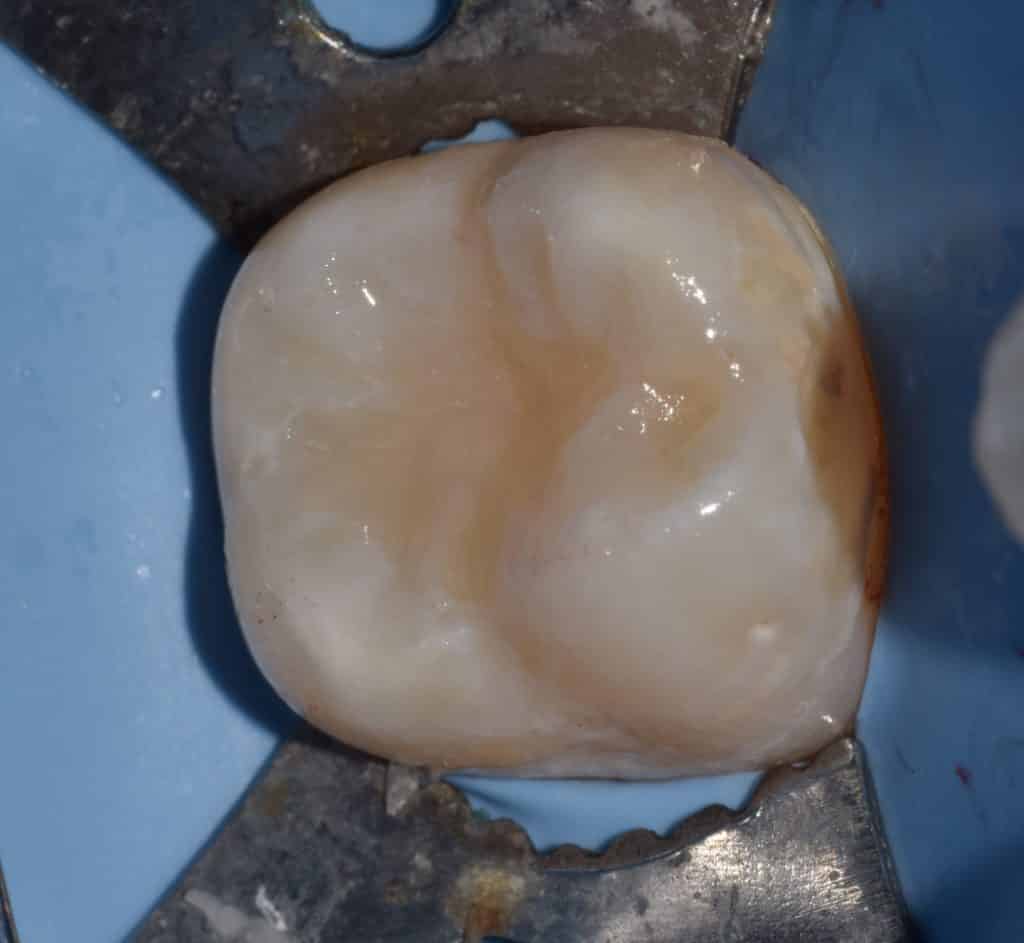

Immediate after final layer

Immediately after rubber dam removal and occlusal check, no need for occlusal adjustment.